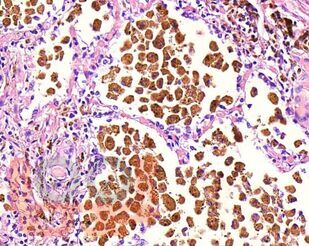

В учебном пособии представлен теоретический материал, перечень макропрепаратов и микропрепаратов, демонстрирующих типовые проявления патологических процессов и нозологических форм заболеваний. В цветных иллюстрациях и в описании микропрепаратов сделан акцент на наиболее важных гистологических изменениях, позволяющих на светооптическом уровне диагностировать и дифференцировать состояния, отклоняющиеся от нормы, в том числе с использованием различных гистологических окрасок. Пособие помогает выделить главные аспекты изучаемых патологических процессов, организовать и конкретизировать учебный процесс.